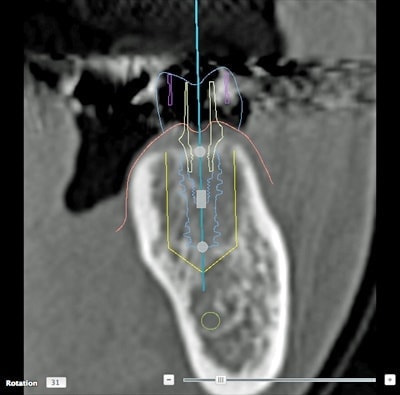

CTによる詳細な現状把握

レントゲンでは把握できないことまでCTでは確認することが出来ます。

身体を断面や立体図として見ることができ、骨はもちろんの事、神経や血管に至るまで確認することができます。

そのデータを元に、どのような角度、どのような深さでインプラントを打ち込むかなど、的確な治療計画を立てることができます。